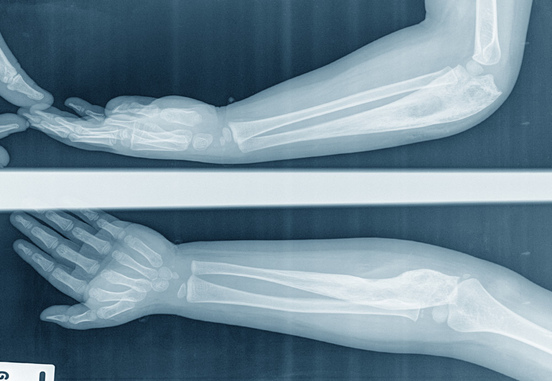

КТ локтевого сустава

Компьютерная томография локтевого сустава исследует анатомическую форму сустава и прилегающих к нему костей. Используется в диагностике травм, остеомиелита, скопления жидкости в суставе и других патологий и состояний.

Что показывает КТ локтевого сустава?

Исследование показывает костные и хрящевые ткани, их структуру, размер и местоположение. Позволяет выявить также метастазы, опухоли и разные аномалии прилегающих костей или мягких тканей.